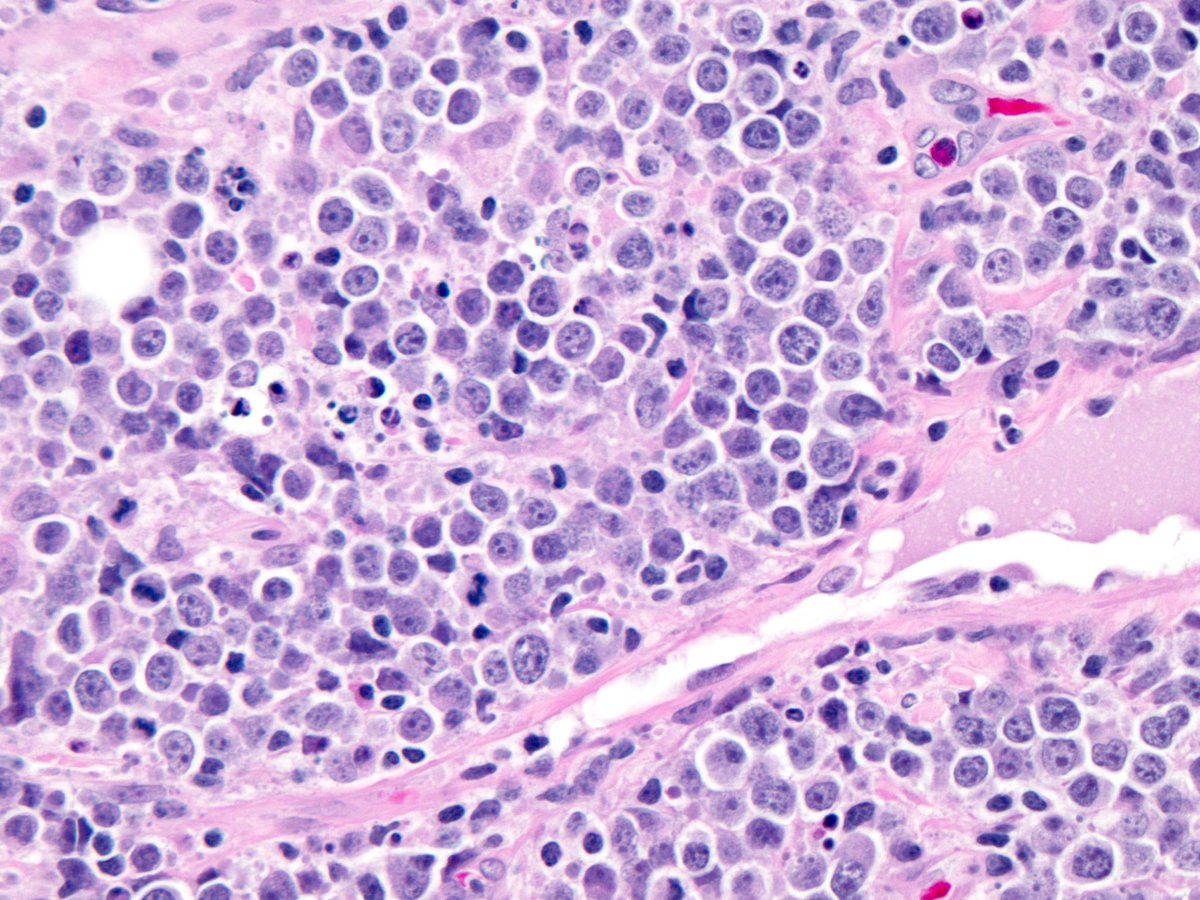

Merkel Cell Tumour Pathology Outlines - PeteBridget

Merkel Cell Tumour Pathology Outlines - PeteBridget petebridget.blogspot.com

merkel pathology tumour mukhopadhyay